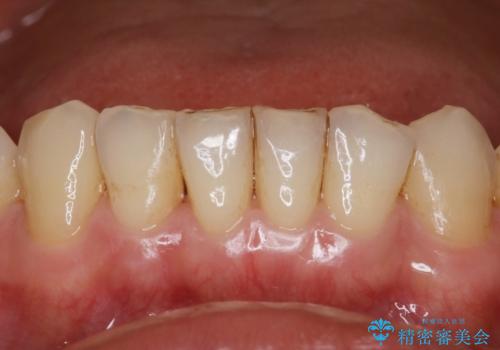

- 治療計画

- インビザラインで矯正中の患者様です。リファインメントのタイミングでホームホワイトニングをご希望でしたが、歯の表面にステインがかなり付着していたため、エアフローでのクリーニングからお勧めしました。

歯の表面にステインやバイオフィルムが付着していると、歯面がざらつき更に汚れが付きやすくなるだけでなく、付着物の影響でホワイトニング薬剤の浸透が悪くなりトーンアップ効果が減少します。歯の表面の汚れを落とすことで歯面もツルツルになり、ホワイトニングを行わなくても歯が白くなった様に感じられる場合もあります。

エアフローだけで歯が白くなったと喜んでいらっしゃいました。新しいマウスピースが届くまでの間はホームホワイトニングを行い歯の内部から白くしていきます。